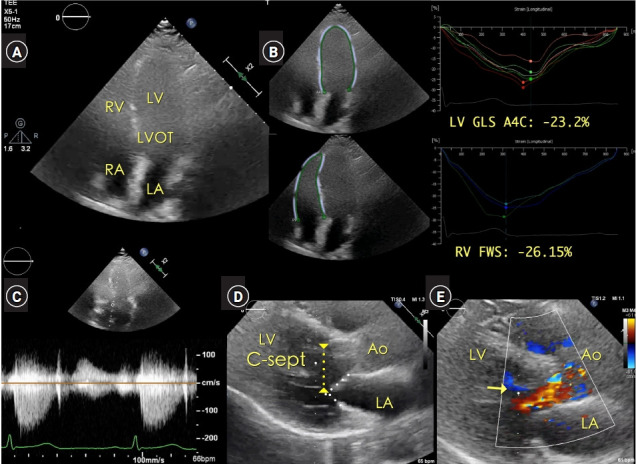

Case: In a 63-year-old female patient undergoing elective thoracic surgery, the systolic murmur was auscultated on the right sternal border of the second intercostal space in the preoperative patient holding area. Point-of-care (POC) transthoracic echocardiography (TTE) demonstrated a systolic jet flow in the LVOT area. The peak systolic velocity of the continuous wave Doppler tracing, aligned to the LVOT and the AV, was approximately 1.5 m/s. The peak/mean pressure gradient was 11/6 mmHg for the AV and 9/5 mmHg for the LVOT. Anesthesia was induced under continuous TTE imaging. Intraoperative transesophageal echocardiography also confirmed the absence of any cardiac pathology.

背景:病例:一名 63 岁的女性患者在接受胸外科择期手术时,在术前病人留置区第二肋间的胸骨右缘听诊到收缩期杂音。床旁(POC)经胸超声心动图(TTE)显示左心室出口区域有收缩期射流。对准左心室出口和房室的连续波多普勒描记的收缩期峰值速度约为 1.5 米/秒。房室的峰值/平均压力梯度为 11/6 mmHg,左心室出口的峰值/平均压力梯度为 9/5 mmHg。在连续 TTE 成像下进行麻醉。术中经食道超声心动图也证实没有任何心脏病变:POC超声心动图为意外发现的收缩期杂音提供了全面的术前评估,避免了传统术前超声心动图评估可能导致的手术时间延迟。